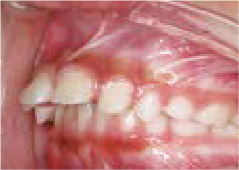

出っ歯

あごや骨格を正しく成長させる矯正治療

Aさん (矯正開始時:8歳)

Before

After

鼻がつまりやすく、口呼吸をしているために上あごが狭い状態でした。また上の前歯がかなり前へ傾いているため、お口をきちんと閉じていることができません。さらに、下の前歯もでこぼこしていました。

治療を終えて

装置によって上あごを拡大し、下あごを少し前へ成長させたことで、永久歯がきれいに並ぶスペースを確保しました。また、お口の機能が向上したことから鼻がよく通るようになり、口呼吸も改善され口も閉じやすくなったので顔の表情もよくなりました。

主訴・治療内容 下あごが後ろに下がり、出っ歯のようになっていることを心配して、無料相談に来院されました。

治療期間 2年半

費用 462,000円(税込)